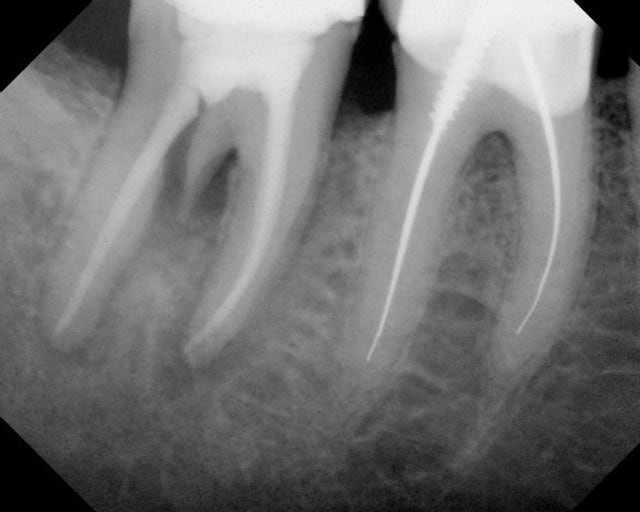

À propos des nécroses en thermocompaction, même avec un cône doublement calibré, test de la lime K du dernier diamètre d' instrument, test de résistance au retrait du cône, tu as des surprises de dépassement de ciment. L'usage de la technique mixte, latérale de un à trois cônes et thermocompacteur résoudra le problème.

La LT du thermocompacteur est 1-2mm de la constriction si tu veux ramollir jusqu'au bout ta gutta ‚ à comparer aux 3-4 de la verticale. Pas de problème si tu respectes les règles et si c'est possible bien sûr ‚ pas de canal courbe.